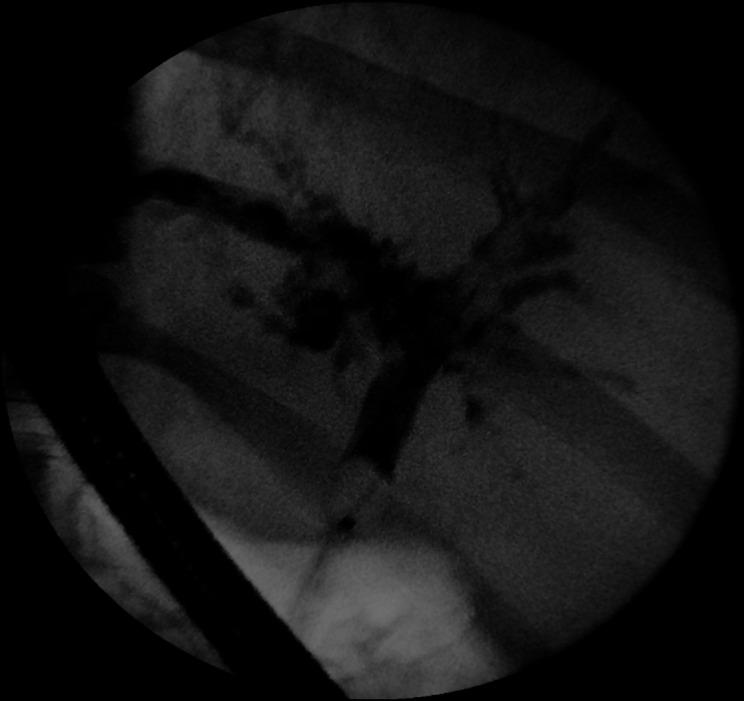

A previously well 59-year-old man required a prolonged intensive care unit stay due to severe COVID-19 symptoms. During the admission, he developed a cytokine storm, also known as secondary haemophagocytic lymphohistocytosis, and multiorgan failure. Despite recovering from his other organ failures, his liver function continued to deteriorate. Magnetic resonance cholangiopancreatography and subsequent endoscopic retrograde cholangiopancreatography revealed extensive intrahepatic duct dilatation with 'beading' but common bile duct sparing. Given the patient had no primary liver disease prior to admission, we considered secondary causes of cholestatic liver injury; this led us to an unusual diagnosis of secondary sclerosing cholangitis in critically ill patients. This case demonstrates a rare disease that has developed specifically in the context of SARS-CoV-2 infection. A review of current literature and the underlying pathophysiology for this rare disease are discussed, particularly in relation to COVID-19.

摘要